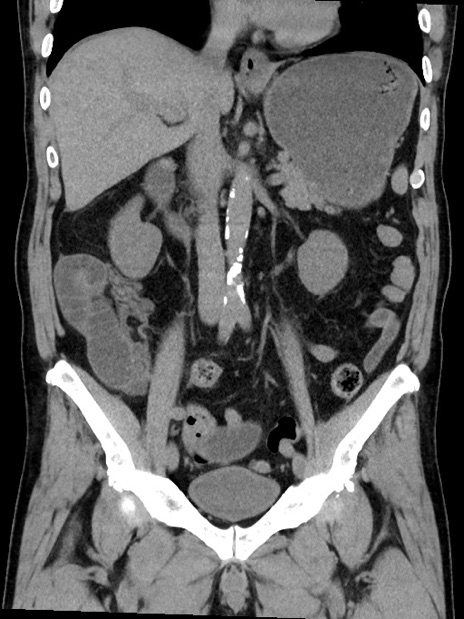

症例35(冠状断像)

【症例】70歳代 男性

【主訴】腹部膨満、嘔吐

【現病歴】昨日より腹部膨満感出現。本日増悪し、仙痛出現。嘔吐あり、受診。

【既往歴】糖尿病、胆摘後

【身体所見】BP 149/80mmHg、HR 74/min、BT 35.9℃、腹部:膨満、軟、圧痛なし。腸雑音減弱あり。上腹部正中切開瘢痕あり。

【データ】WBC 13500、CRP 1.72